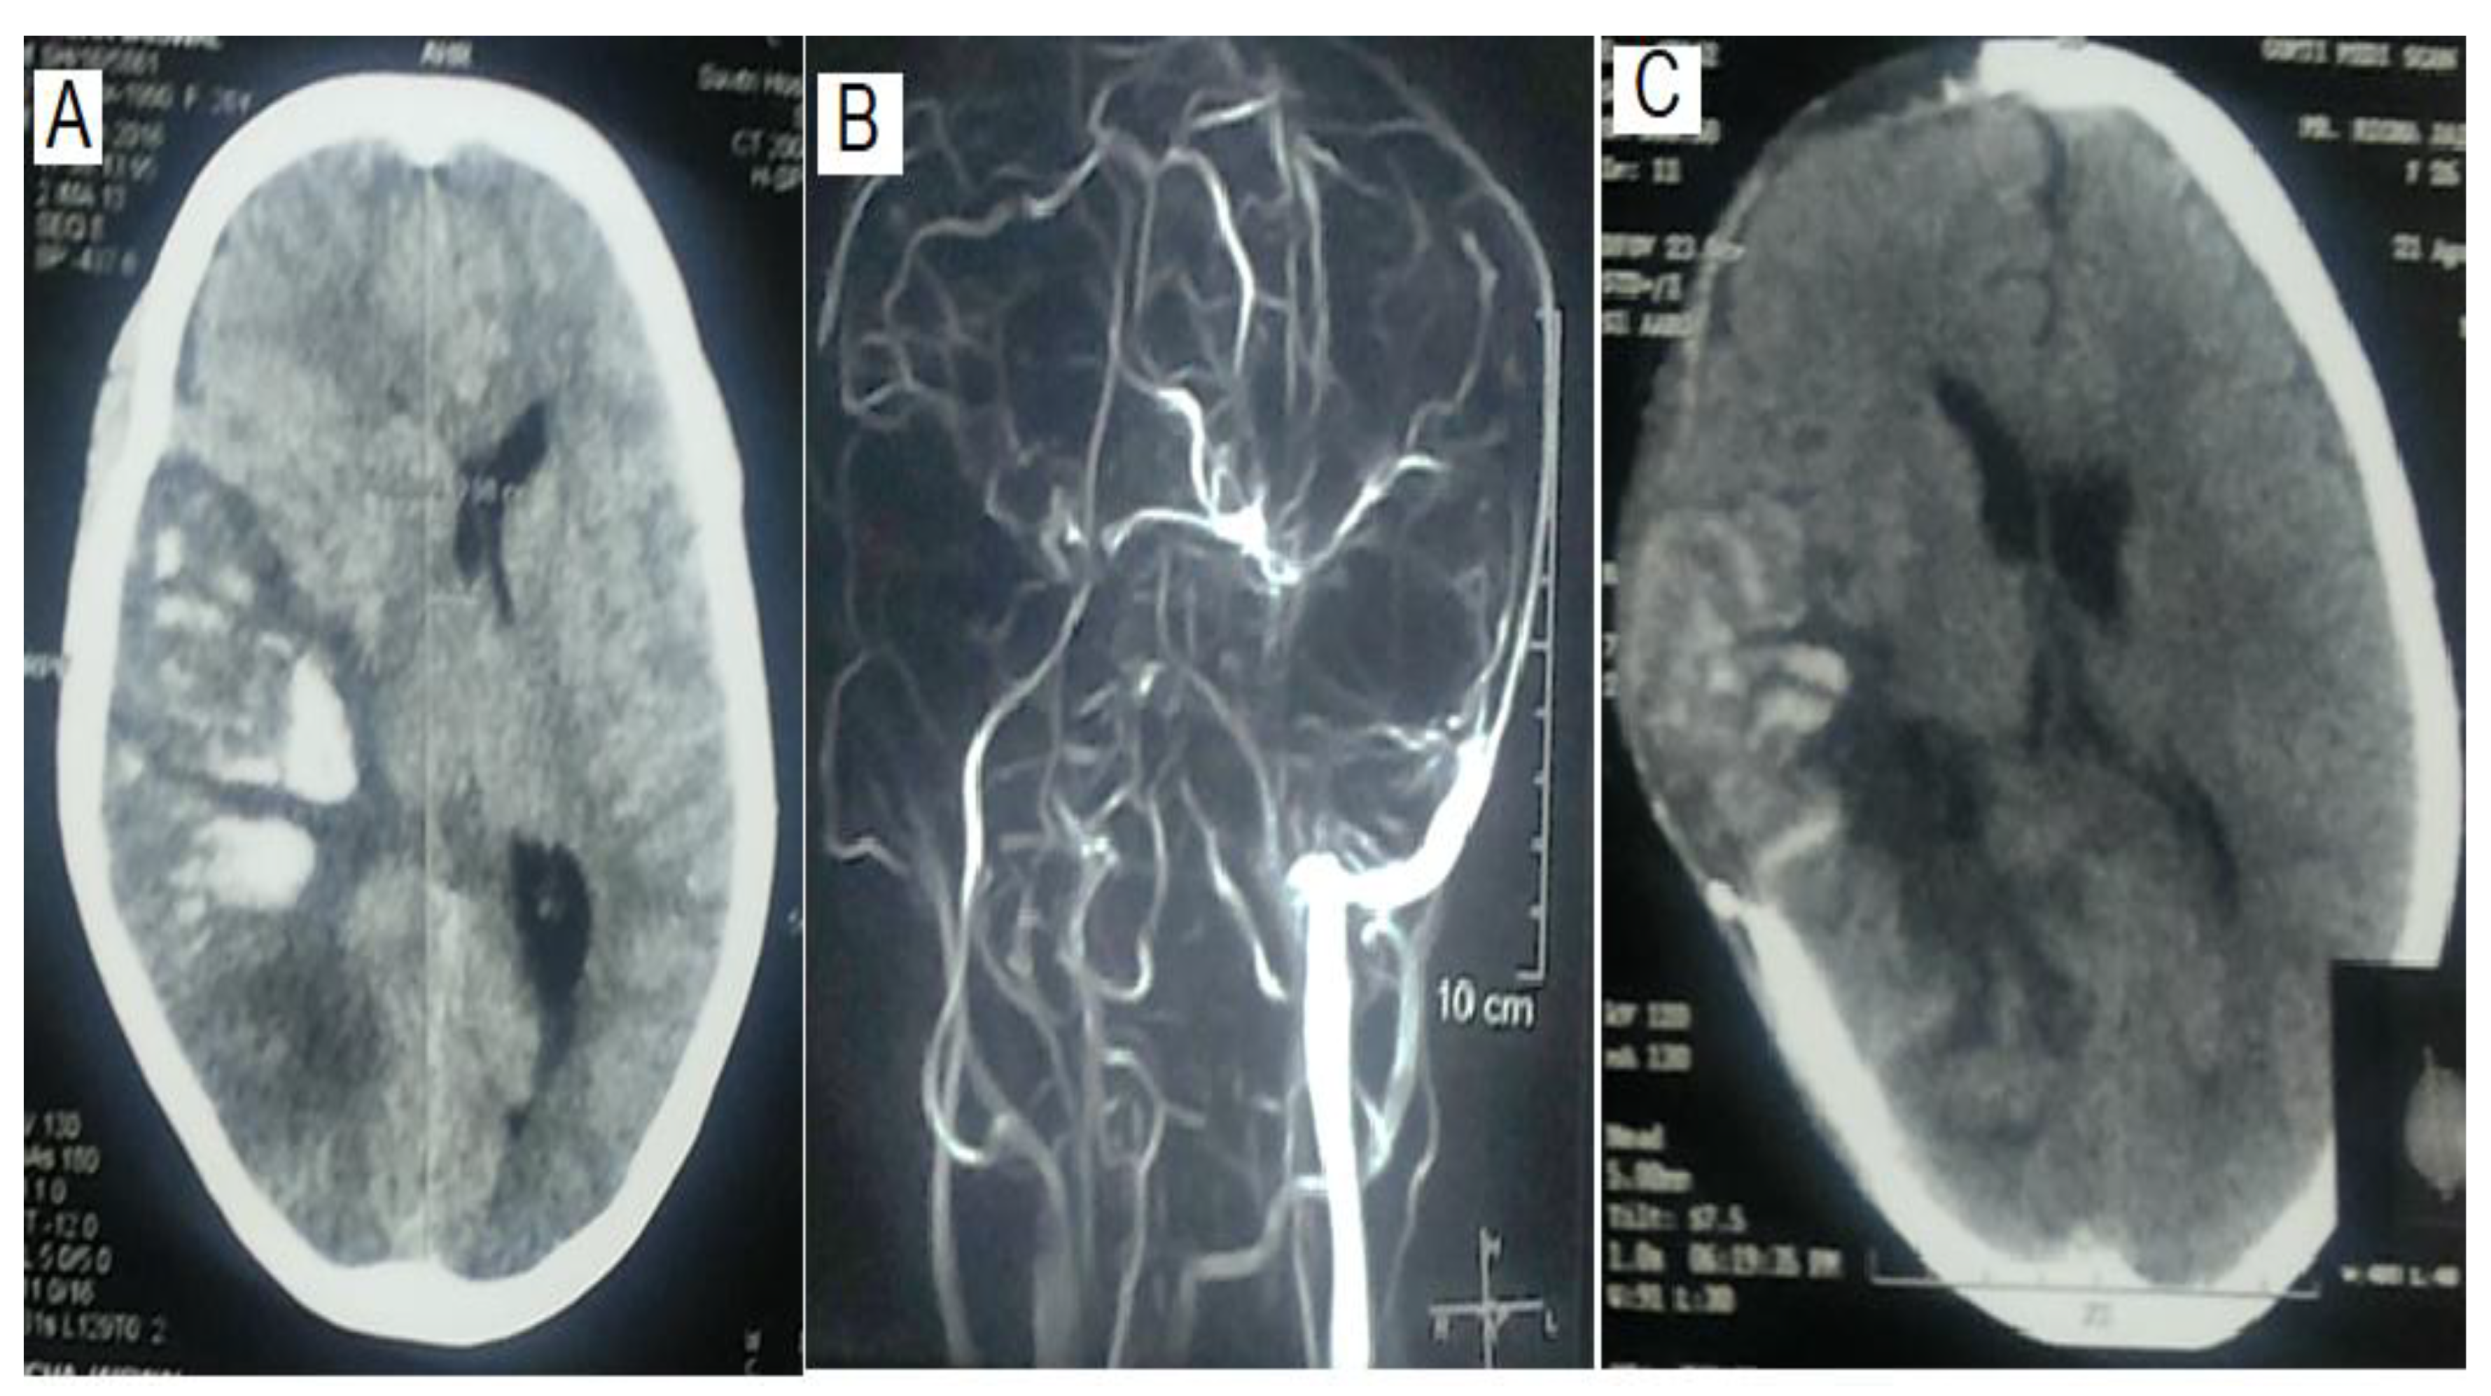

The location and extent of thrombosis did not determine the requirement of MV. Both MV and Non-MV groups had comparable numbers of sinus thrombosis (1.33±0.48 vs 1.26± 0.45; P=0.60). Superior sagittal sinus was the commonest site of thrombosis (n=31, 68.9%) followed by transverse (n=29, 64.4%) and sigmoid (n=19, 42.2%), which were also not different in MV and non-MV groups (Table 2, Figure 1). The presence of a parenchymal lesion (16 Vs 23; P = 1.00) and frequency of hemorrhagic (15 Vs 17) and pale infarctions (1 Vs 6) were also comparable between MV and non-MV patients (P = 0.21).

Figure 1. CT scan and MR venography of a patients with cerebral venous thrombosis showing haemorrhagic infarction on the parieto-occipital area with effacement of sulci and ventricle, and midline sift (A). On MR venography, there was thrombosis of both superficial and deep system. C) The patient underwent hemicraniectomy on 3rd day of hospitalization, and post operative CT scan revealed improvement in mass effect as evidenced by reappearance of lateral ventricle and reduced midline shift.